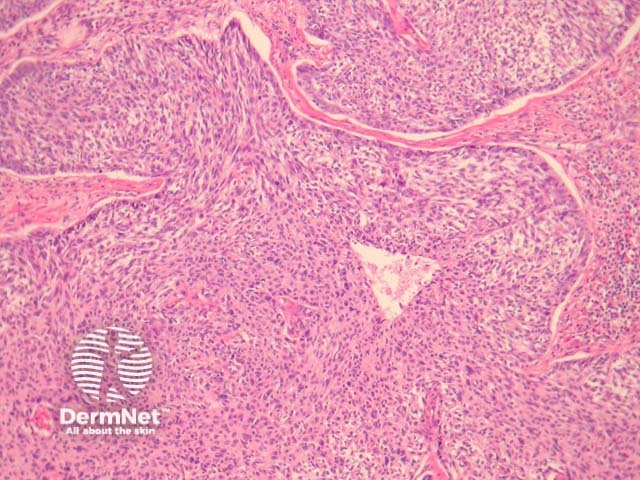

Low power examination of malignant basomelanocytic tumour show an infiltrating dermal tumour with features of a basal cell carcinoma replete with peripheral palisading and retraction around the tumour islands (figure 1). Higher power magnification may be needed to identify malignant melanocytes. Prominent nucleoli can be a helpful feature as these are not typically seen in regular basal cell carcinomas (figure 2).

Figure 1